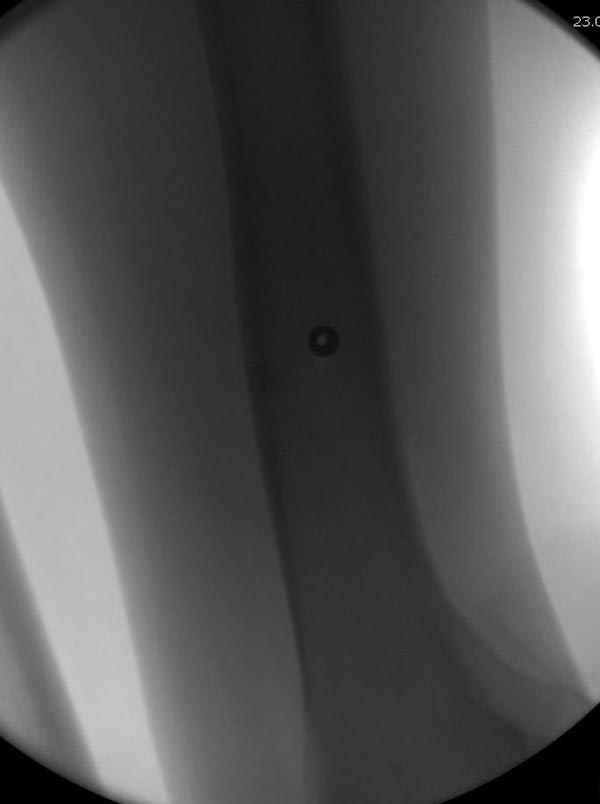

Методика штифтования при отсутствии большой зоны перелома как при онкологических профилактических штифтованиях, расверливание интрамедуллярного канала проводим с предварительным наложением дополнительного дренажного отверстия в дистальном отделе бедра (в данном случаи в канале оставили 6.5 мм канюлированный шуруп), иначе при создании давления в канале во время сверления имеется опасность эмболизации легочной артерии тромбом.